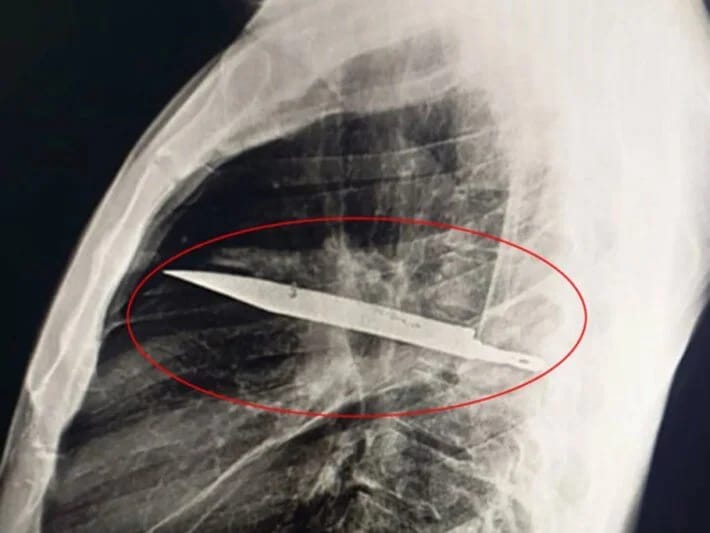

Ağrıdan şikayət edərək xəstəxanaya getdi, sinəsindən bıçaq tapıldı

7NEWS.az xəbər verir ki Tanzaniyada ağrı şikayəti ilə xəstəxanaya gedən kişinin səkkiz ildir sinəsində bıçaqla yaşadığı məlum olub.